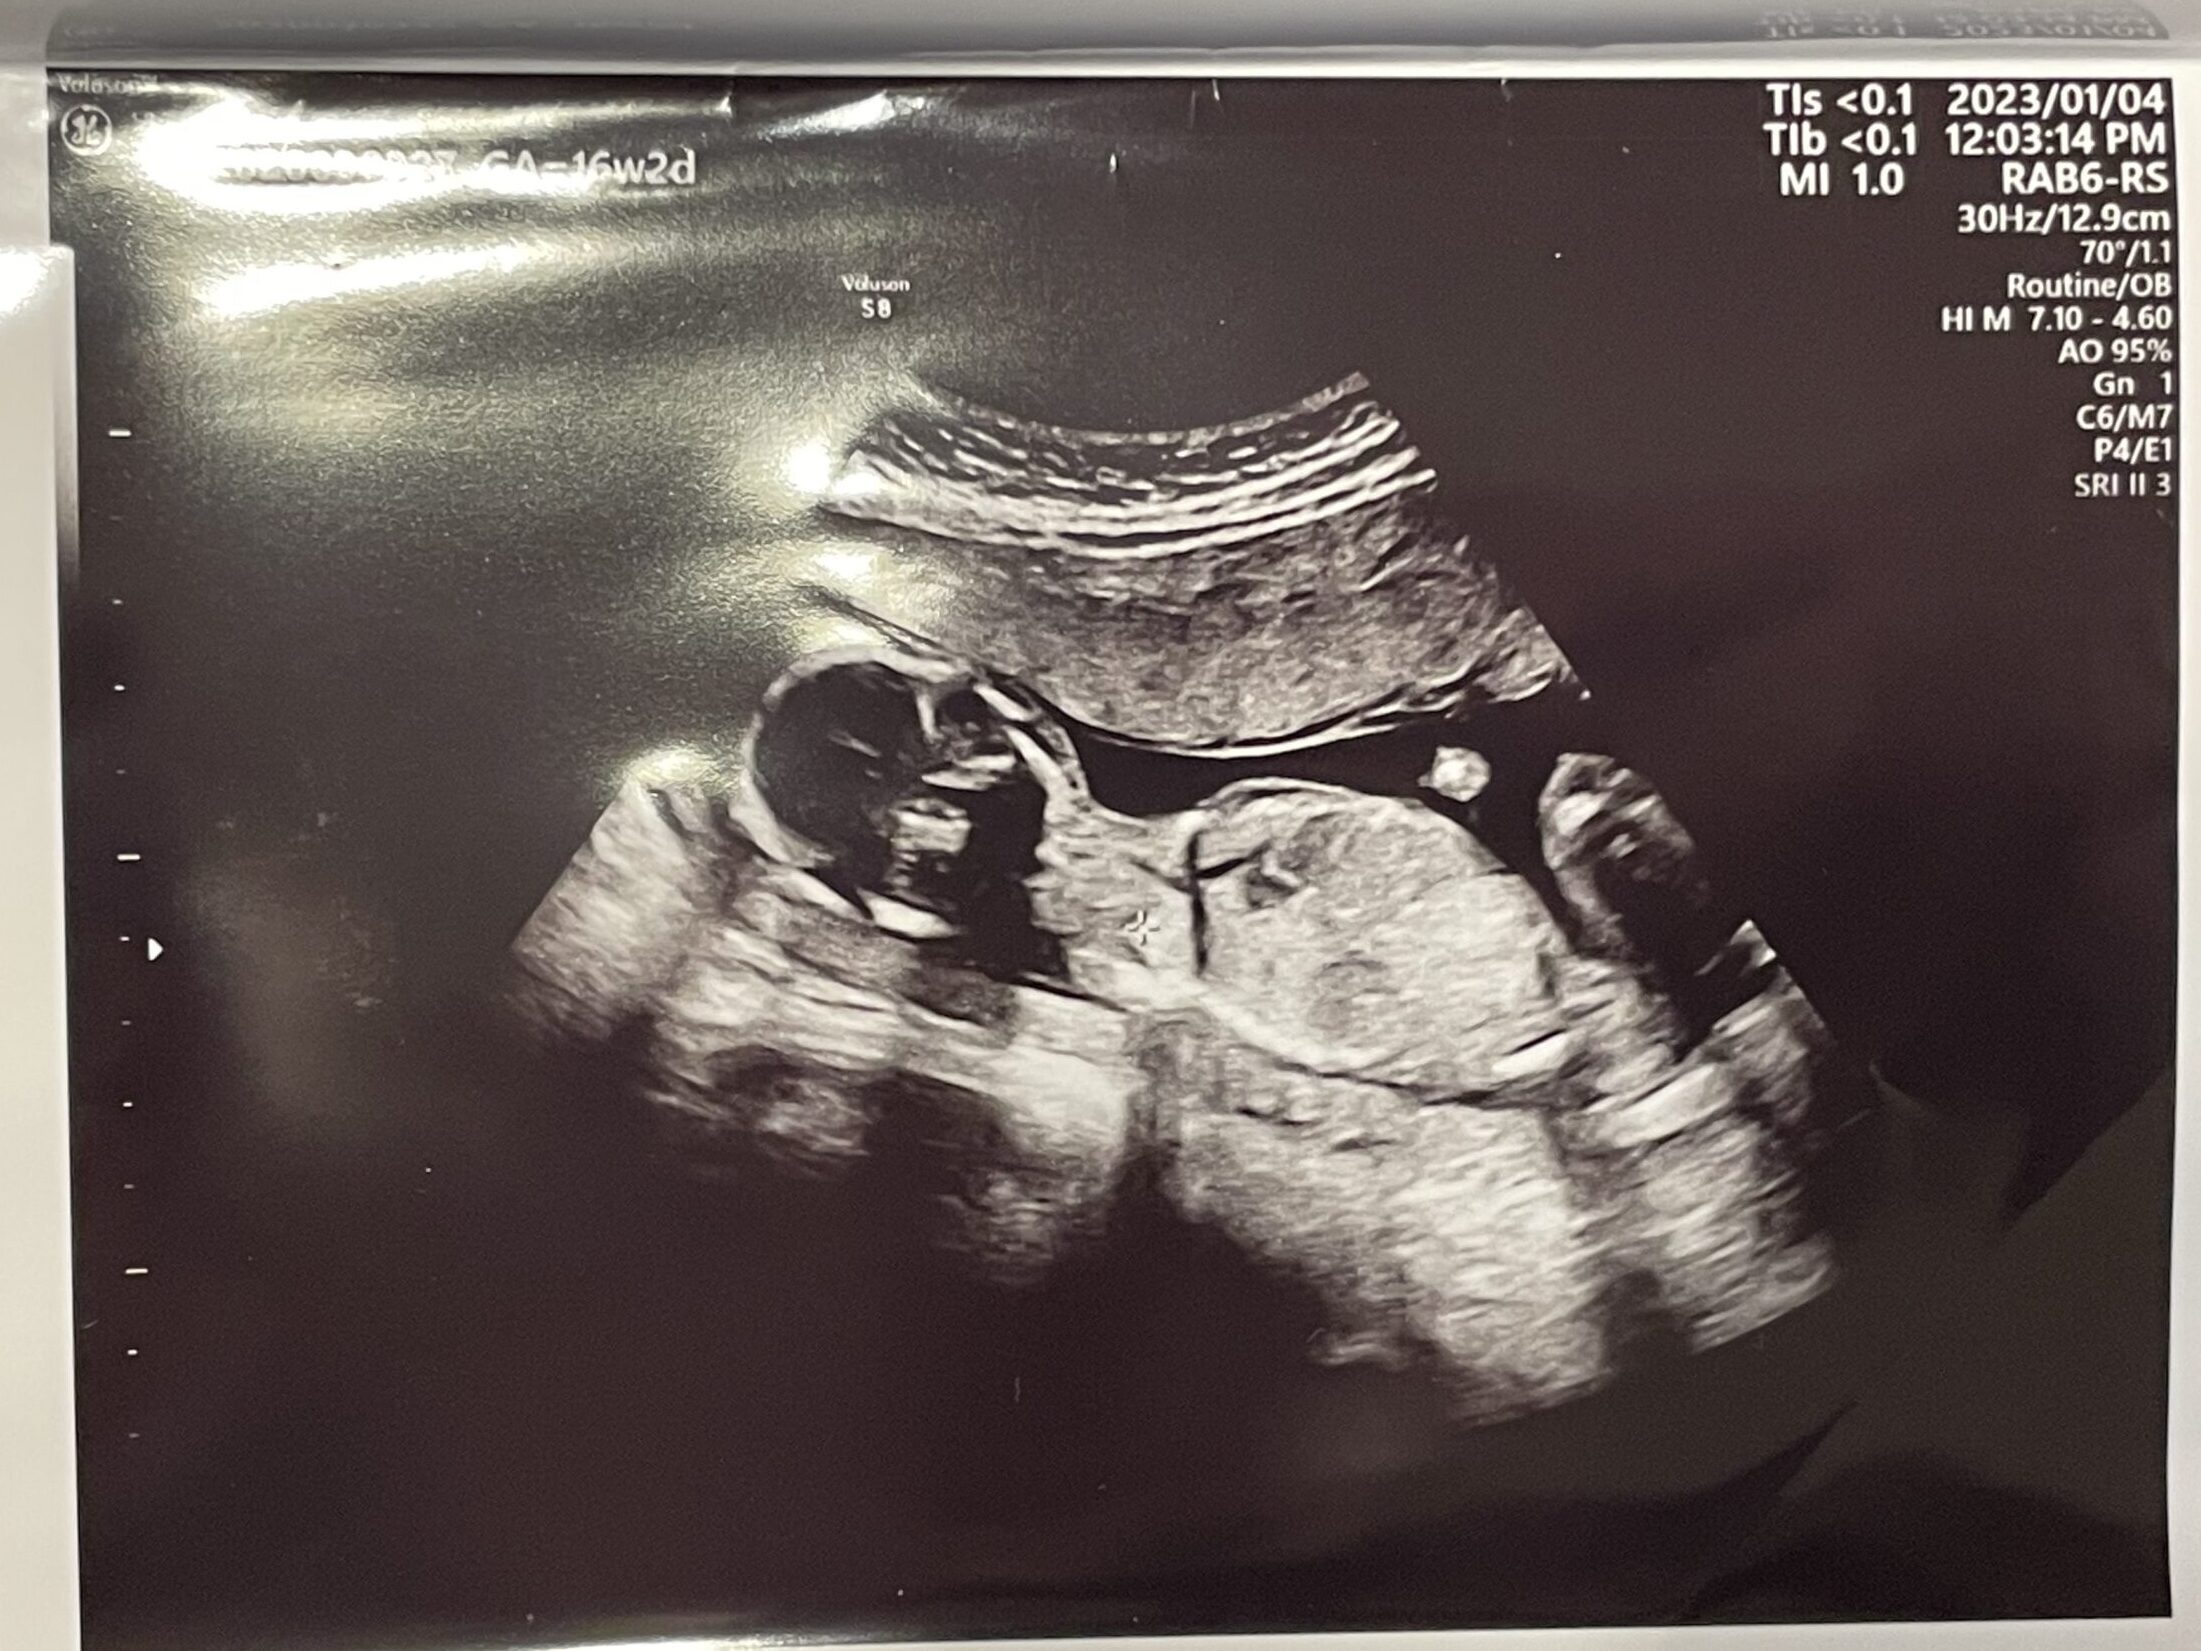

希望したわけではないのですが、お腹からの普通のエコーに加えて途中から4Dに切り替えて見せてくれました。

今日、性別がわかるのかなー?!とドキドキしていたのですが、次回の詳しい超音波検査(スクリーニング検査)の時にわかるとのことでした。

今日お医者さんもわかっていたけど、より確信的なことを伝えるために次回のスクリーニング検査の時にわかるっていったのかなと思いました。だってお医者さん、足の間らしきところとかもみてたもの!笑

わたしの予想は、女の子かな?です。次回がより一層楽しみになりました^^